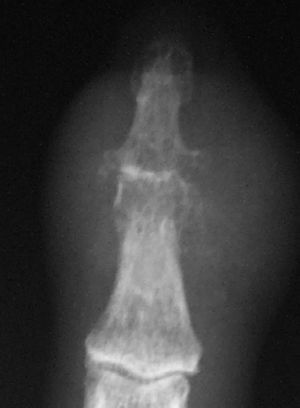

En las radiografías de las manos se apreciaron cambios degenerativos en las articulaciones metacarpofalángicas, interfalángicas y trapeciometacarpianas. La interfalángica distal del segundo dedo presentó aumento de partes blandas, con disminución del espacio articular y erosiones en sacabocados (fig. 1). La ecocardiografía y los hemocultivos seriados fueron negativos.